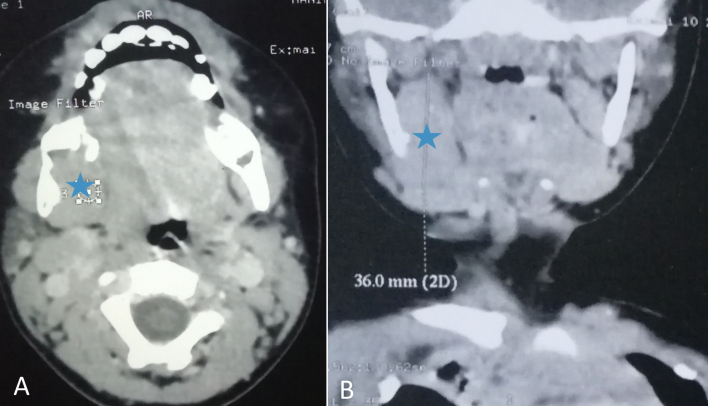

Case presentation: We report a rare case mandibular IDF, highlighting its clinical features and management. A two-year-old child with no known medical history, presented with a 5-month history of a right lateral cervical mass. Physical examination revealed a fixed 3 cm mass in the sub-mandibular region. Cervical computed tomography showed a 4 cm heterogeneous lesion at the right mandibular angle, with bone lysis and contact with the ipsilateral submandibular gland and the hyoid bone. A biopsy was performed and histological examination confirmed the diagnosis of an IDF. The patient underwent a wait and see approach, and after two years of follow-up, both clinical and ultrasound evaluation showed a significant regression of the mass, with no associated symptoms. No artificial intelligence (AI) tools were used in the research, analysis, or writing of this manuscript.